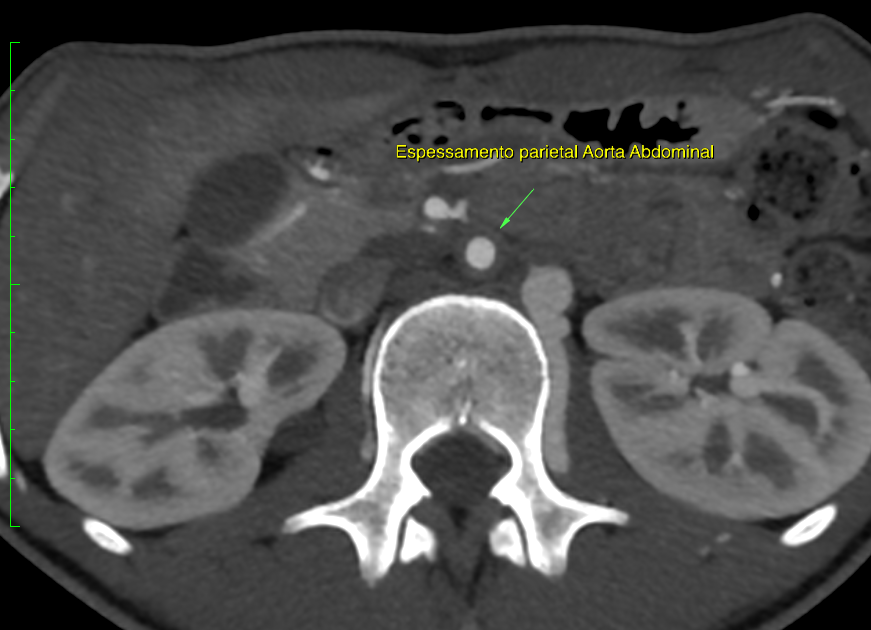

A livello microscopico si possono distinguere due fasi di malattia: una fase acuta ove si evidenzia un infiltrato di macrofagi, linfociti e plasmacellule organizzato come una semplice invasione perivascolare, rispetto ai vasa vasorum, fino a un'intensa risposta granulomatosa con cellule giganti e necrosi non caseosa centrale; nella fase in via di guarigione esita in un ispessimento irregolare della parete vascolare con iperplasia intimale e fibrosi trans-murale retraente. A livello macroscopico si notano gli esiti della patologia attraverso l'ispessimento della parete vascolare con restringimento luminare dei grossi vasi. Quest'interessamento può essere segmentale o multifocale e associato a tenaci aderenze esterne. L'ostruzione può determinare obliterazione degli osti delle arterie collaterali.